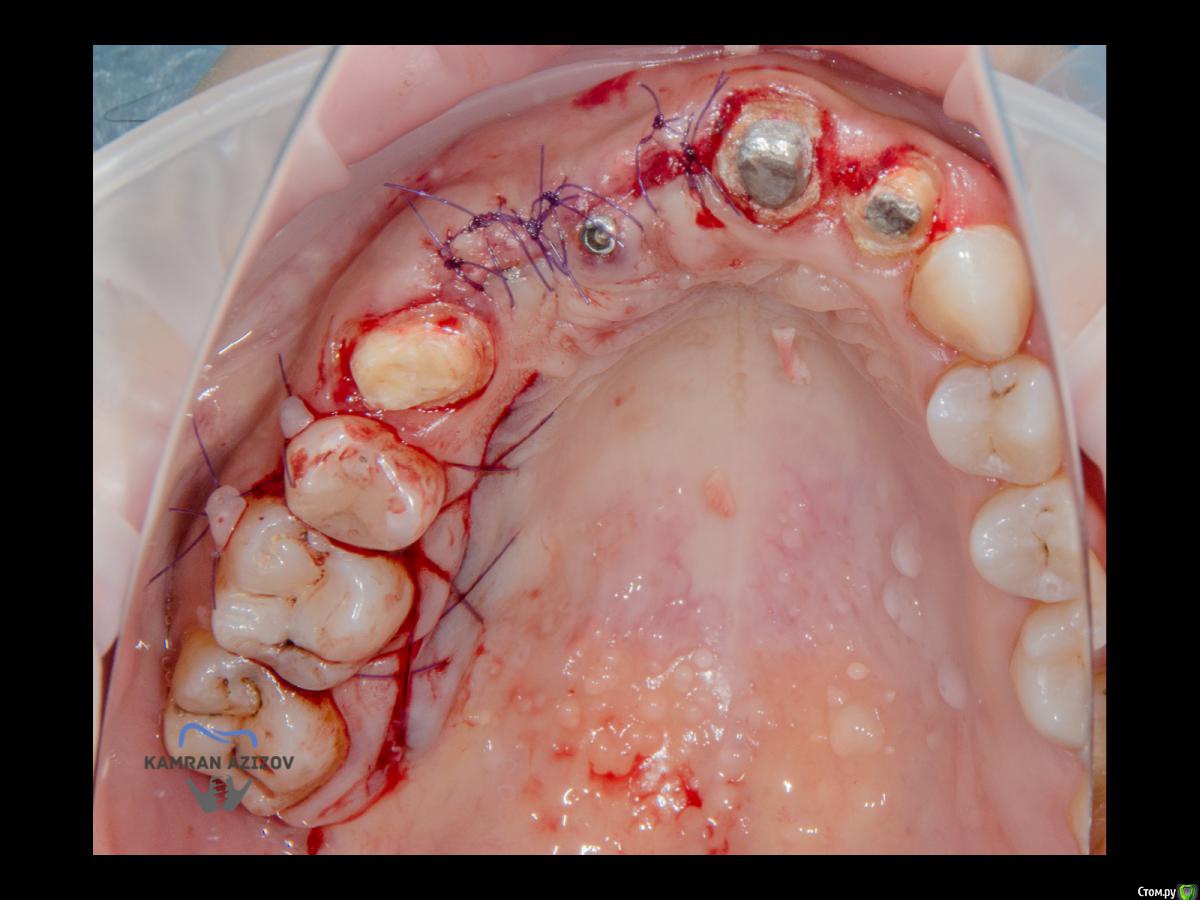

kamranchick Опубликовано 6 апреля, 2019 Поделиться Опубликовано 6 апреля, 2019 (изменено) Хай Гайсдавно ничего не комментировал и не выкладывал, что то настроения не было, да и муза не посещалаСитуация следующаяпришла пациентка, жалобы на неприятный запах из рта, сначала не понял что за хрень, ну как распилил мост понял че к чему... халтура.Ну и по кейсуУдаление клыка и 2ки, через 2 месяца навигация, имплантация + Шашлыки по карлоссу, смена формиков, временное протезирование. только мягкие ткани, Изменено 6 апреля, 2019 пользователем kamranchick 7 1 Ссылка на комментарий

Nazim_NV86 Опубликовано 7 апреля, 2019 Поделиться Опубликовано 7 апреля, 2019 Пятый Без пина шаблон не держался? Ссылка на комментарий

kamranchick Опубликовано 8 апреля, 2019 Автор Поделиться Опубликовано 8 апреля, 2019 Пятый Без пина шаблон не держался? держался) но сделали на всякий случай) Ссылка на комментарий